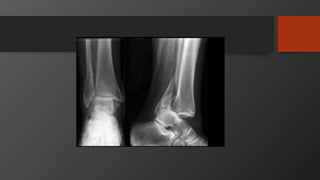

Ankle Fractures

Imaging

• AP, Lateral

• Mortise view

• CT scan

• Especially posterior malleolus